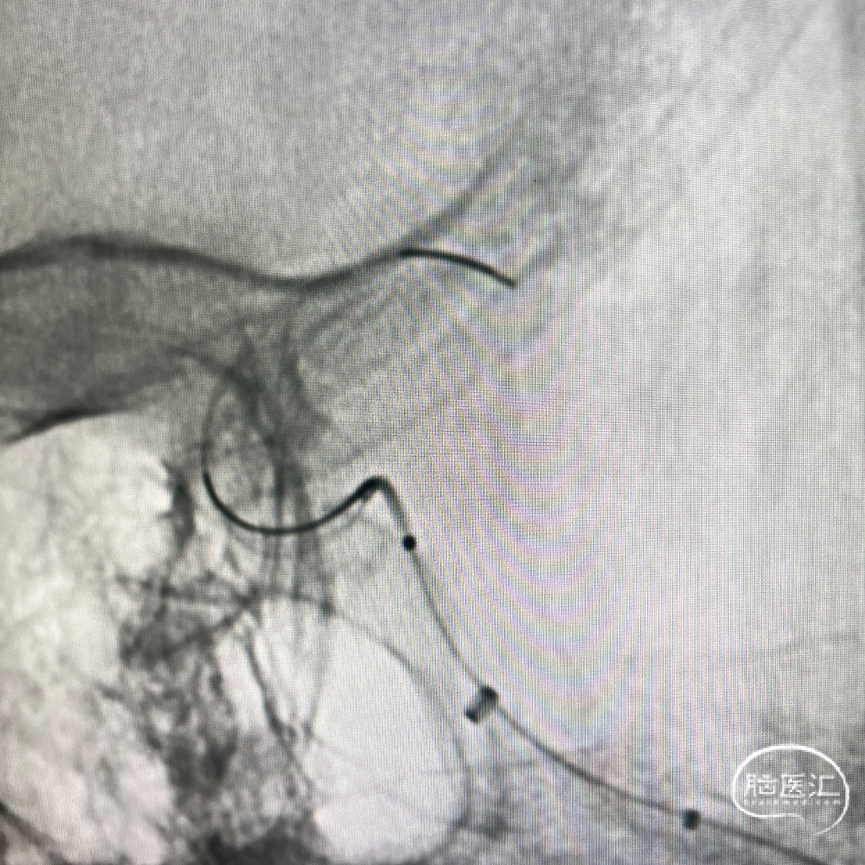

泰杰Frepass® TJMC18Plus支架微导管、6F 中间导管同轴上高,微导丝引导泰杰Frepass® TJMC18Plus支架微导管顺利上高至大脑中动脉M1平直段。微导丝引导栓塞微导管顺利进入瘤内。

输送Nuva®血流导向密网支架 TJED-D-5.5-20顺利到位,释放头端及定位支架远端。

继续释放Nuva®血流导向密网支架。

密网支架半释放状态下,沿栓塞微导管顺利填入泰杰Perfiller®栓塞用可膨胀弹簧圈系统 9mm*30cm ,然后撤出栓塞微导管。

完全释放支架后即刻造影,可见支架贴壁良好。